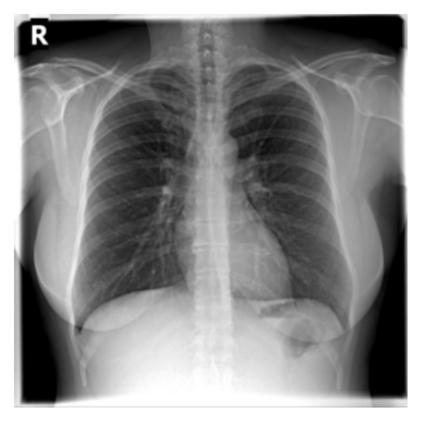

The evaluation of infectious disease processes on radiologic images is an important and challenging task in medical image analysis. Pulmonary infections can often be best imaged and evaluated through computed tomography (CT) scans, which are often not available in low-resource environments and difficult to obtain for critically ill patients. On the other hand, X-ray, a different type of imaging procedure, is inexpensive, often available at the bedside and more widely available, but offers a simpler, two dimensional image. We show that by relying on a model that learns to generate CT images from X-rays synthetically, we can improve the automatic disease classification accuracy and provide clinicians with a different look at the pulmonary disease process. Specifically, we investigate Tuberculosis (TB), a deadly bacterial infectious disease that predominantly affects the lungs, but also other organ systems. We show that relying on synthetically generated CT improves TB identification by 7.50% and distinguishes TB properties up to 12.16% better than the X-ray baseline.